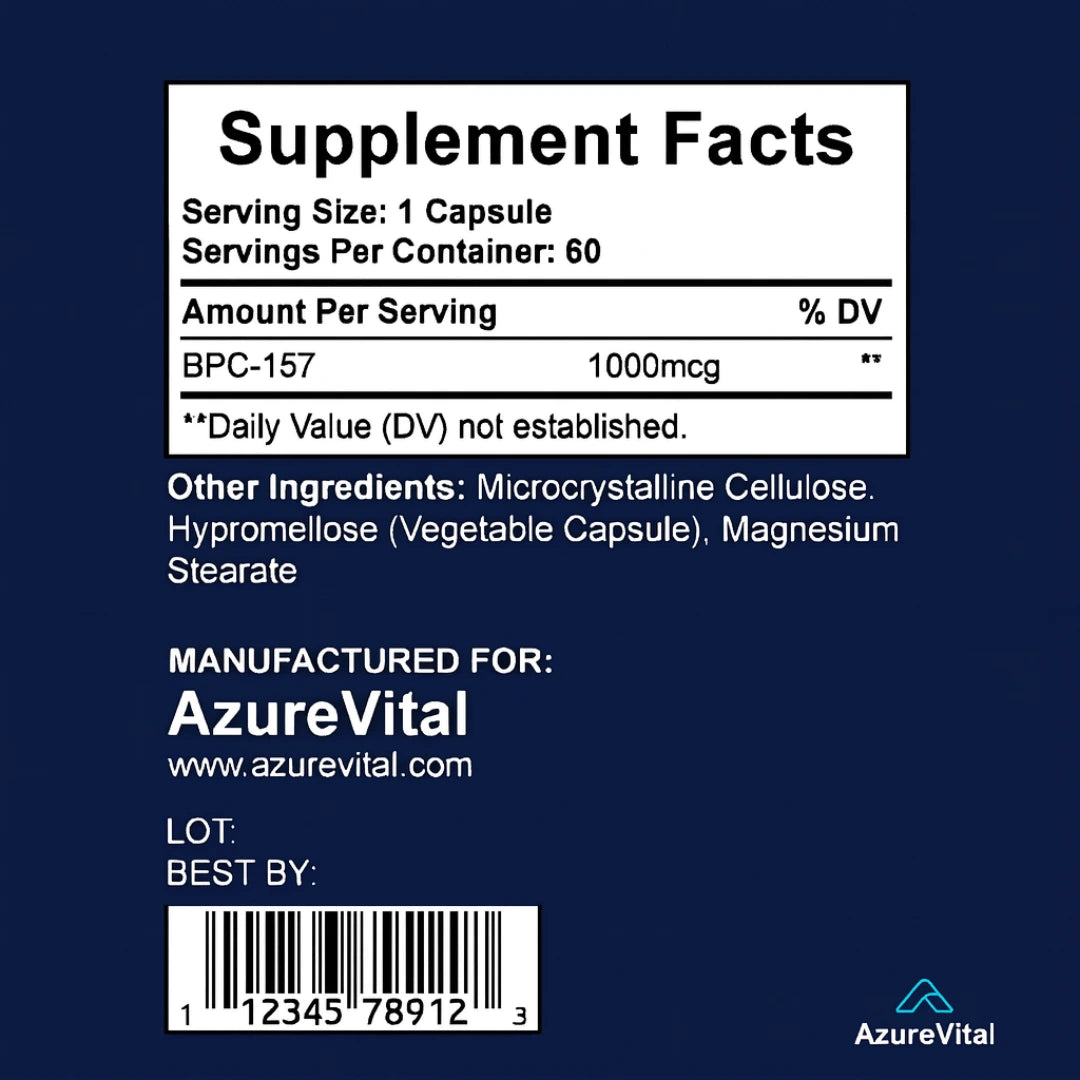

2. What are the ingredients in BPC-157?

2. What are the ingredients in BPC-157?

Each serving contains 1000mcg of BPC-157 , which includes amino acids such as L-Valine, L-Glutamine, L-Glycine, L-Proline, L-Lysine, and others. The capsule is made from vegetable cellulose, and the formula is vegan, non-GMO, sugar-free, and dairy-free.

3. What is the recommended daily dosage?

3. What is the recommended daily dosage?

The recommended serving is 1000mcg daily, typically taken as 1-2 capsules per day (based on the full-dose version shown in the label). For your version, use the suggested dose on your packaging or consult with your healthcare provider.